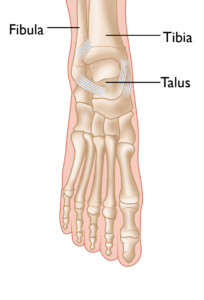

Pediatric ankle fractures, commonly referred to as broken ankles, are among the most frequent injuries in children. These fractures involve a break in one or more bones of the ankle joint: the tibia (shinbone), the fibula (outer ankle bone), or the talus (a small bone located at the back of the foot).

Anatomy of the Ankle Joint

The ankle joint is the point where the tibia (shinbone), fibula (outer ankle bone), and talus (a small bone in the foot) come together. These bones are held in place by ligaments, which function like sturdy ropes, providing stability to the joint by connecting bones and preventing excessive movement. The ankle contains several important ligaments that work together to maintain joint stability and facilitate smooth movement.

The normal skeletal anatomy of the foot and ankle.